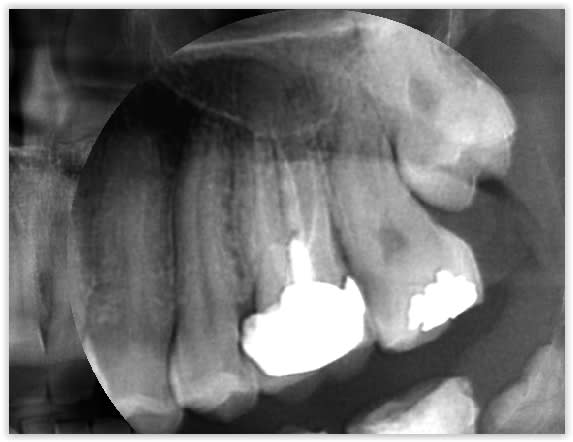

Quelques photos prises ce matin au cours d'une longue séance de soins. Je posterais un test complet de la caméra bientôt pour ceux que ça intéresse...

A priori la résolution native de la caméra est de 640*480, donc pas du tout HD... Les soit disant 2 mega pixels sont obtenus par upscaling purement logiciel.

C'est une petite supercherie que beaucoup de caméra intra-orale chinoise utilise.